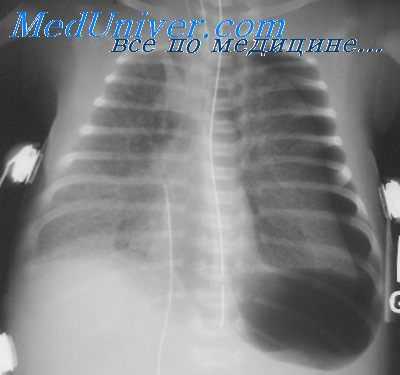

В одной серии наблюдений, включающей 88 больных с баротравмой легких, газ поступает в разорванные легочные сосуды, а затем в системную циркуляцию крови, вызывая в 75% случаев объективные и субъективные проявления нарушений ЦНС [Elliott et al., 1978].

Газ, который проникает в разорванные сосуды перегородок альвеол, далее мигрирует через легочные вены в левое предсердие и левый желудочек, а затем изгоняется в систему циркуляции в вид вспененных частиц, которые распределяются по кровеносному руслу в соответствии со степенью их плавучести. В обычном вертикальном положении тела весь объем эмболического газа поступает в мозг, в то время как в обратном положении с поднятыми вверх ступнями эмболизируются преимущественно коронарные сосуды.

В противоположность неврологической форме болезни декомпрессии, возникающей при субнасыщенном погружении, основным органом-мишенью при дисбарической артериальной газовой эмболии является головной мозг, признаки его дисфункции доминируют в клинической картине заболевания. Эмболизация газом артерий и артериол вызывает как дистальную ишемию, так и прямое повреждение эндотелия в месте обструкции, которое не опосредованно исключительно гипоксией или ишемией.